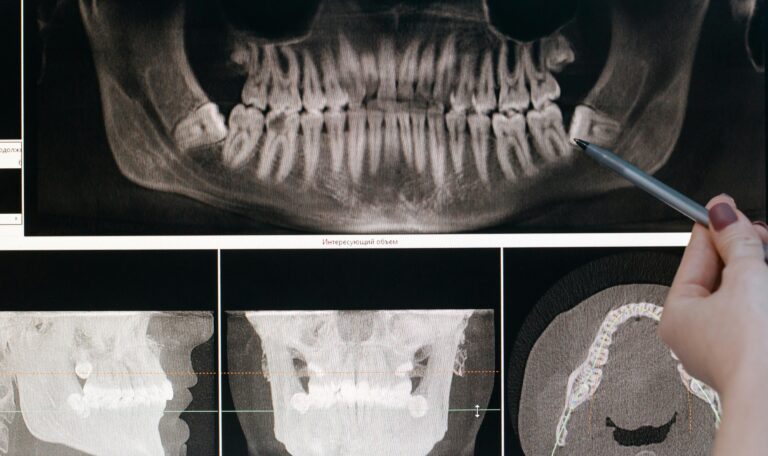

Realizamos una revisión clínica detallada, fotografías, radiografías scaner y análisis de la mordida para determinar el plan de tratamiento más adecuado.